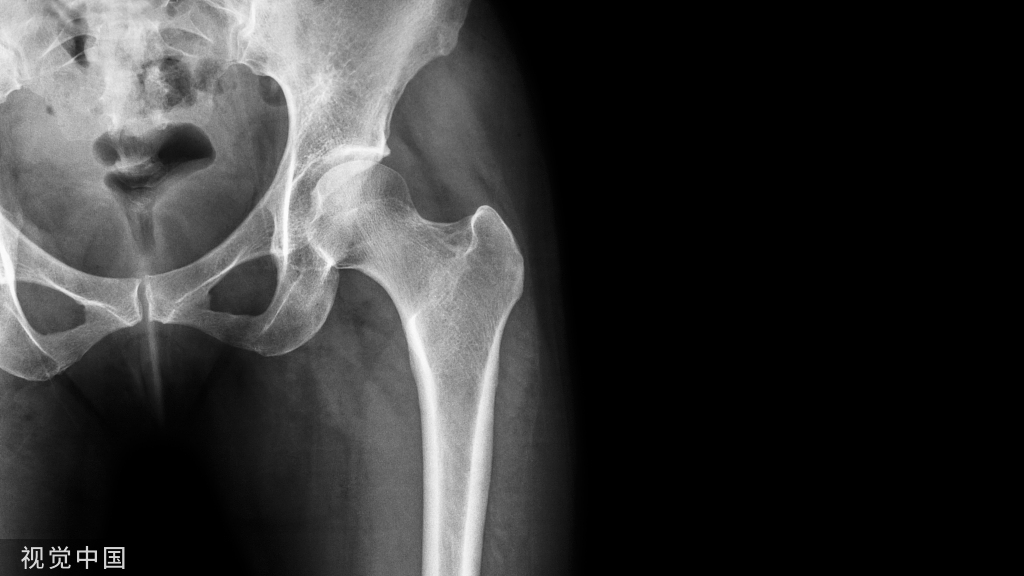

一项研究称,男性吸烟者的骨质疏松风险高于其他男性,甚至高于女性吸烟者。该数据还显示,如果男性患有骨质疏松且出现髋部骨折,他们的病情将比女性更严重。

Regan博士及其同事检查了3321名目前及以往吸烟人群的骨密度和肺部疾病严重程度,并诊断是否有椎体骨折。研究还纳入63名不吸烟的人群作为对照。

研究人员发现,尽管男性吸烟者骨密度低的程度较轻,但相比女性吸烟者,骨密度低的风险显著升高,且椎体骨折率更高。有58%的研究参与者出现骨质疏松的临床表现,其中84%的人患有慢性阻塞性肺部疾病。

有37%的研究参与者有1处或以上的椎体骨折,其中大部分为男性,年龄较大,有很长时间的吸烟史且现在仍在吸烟。